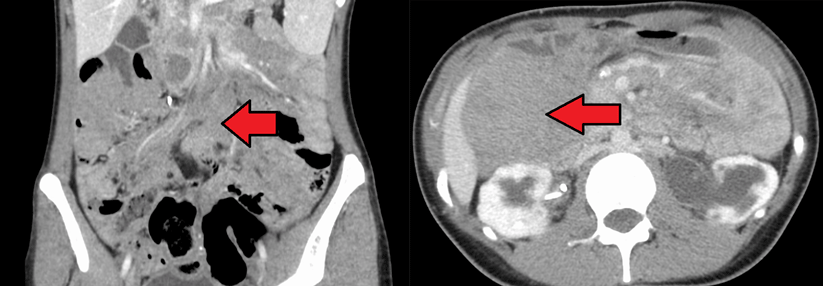

Desmoid-Tumoren sind sehr heterogen und müssen individualisiert behandelt werden. Sie können lokal aggressiv wachsen und mit einer hohen Symptomlast einhergehen. Deshalb sind sowohl das Verhindern eines Progresses als auch das Lindern der Beschwerden wichtige Therapieziele. Zum ersten Mal wurde nun der Notch-Singalweg erfolgreich inhibiert.

Desmoide Tumoren treten selten auf und sind sehr heterogen, was die Therapie erschwert. Der γ-Sekretase-Hemmer Nirogacestat blockiert den Notch-Signalweg, der in dieser Krebsentität stark hochreguliert ist. „Das ist die erste positive Phase-3-Studie bei Desmoid-Tumoren“, hob Professor Dr. Bernd Kasper vom Krebszentrum der Universitätsmedizin Mannheim die Bedeutung der Studie hervor.

An der DeFi-Studie nahmen weltweit 142 Patient:innen mit einem histologisch bestätigten Desmoid-Tumor und Progress nach RECIST-Kriterien teil. Das mediane Alter lag bei etwa 34 Jahren, Frauen waren überrepräsentiert, wie es für diese Erkrankung laut Prof. ­Kasper typisch ist. Die meisten litten unter einem…